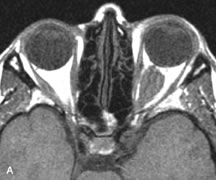

NORMAL ORBITAL ANATOMY

T1-weighted images provide the best anatomic details of the orbit because they display superior contrast resolution between normal structures (see Fig. 8). The vitreous has a long T1, resulting in an intermediate signal similar to brain, whereas the crystalline lens and sclera appear dark because of a longer T1 and short T2. The extraocular muscles, like all skeletal muscles, demonstrate a moderately long T1 and short T2 and highly contrast with the intense signal of the surrounding orbital fat (adipose tissue has an extremely short T1). The lacrimal glands appear as mottled areas of reduced intensity of the signal from the orbital fat in the lacrimal fossa. The optic nerves are seen with the same signal intensity as brain white matter and are hypointense relative to the orbital fat because their Tl is longer than the Tl of fat but shorter than the Tl of water.

Cortical bone is not well delineated because it contains little free water, yielding minimal signal in MRI, and thus appears dark on all pulse sequences. This feature explains why MR images of the orbital apex and intracanalicular portion of the optic nerves are superior to comparable CT scans. Partial volume averaging of the bones in these regions obscures soft tissue details on CT images, whereas MRI reveals the signals only from the soft tissue structures with no cortical bone input. Bone marrow, on the other hand, is seen as a relatively intense signal because of its high fat content (see Fig. 8).37,38